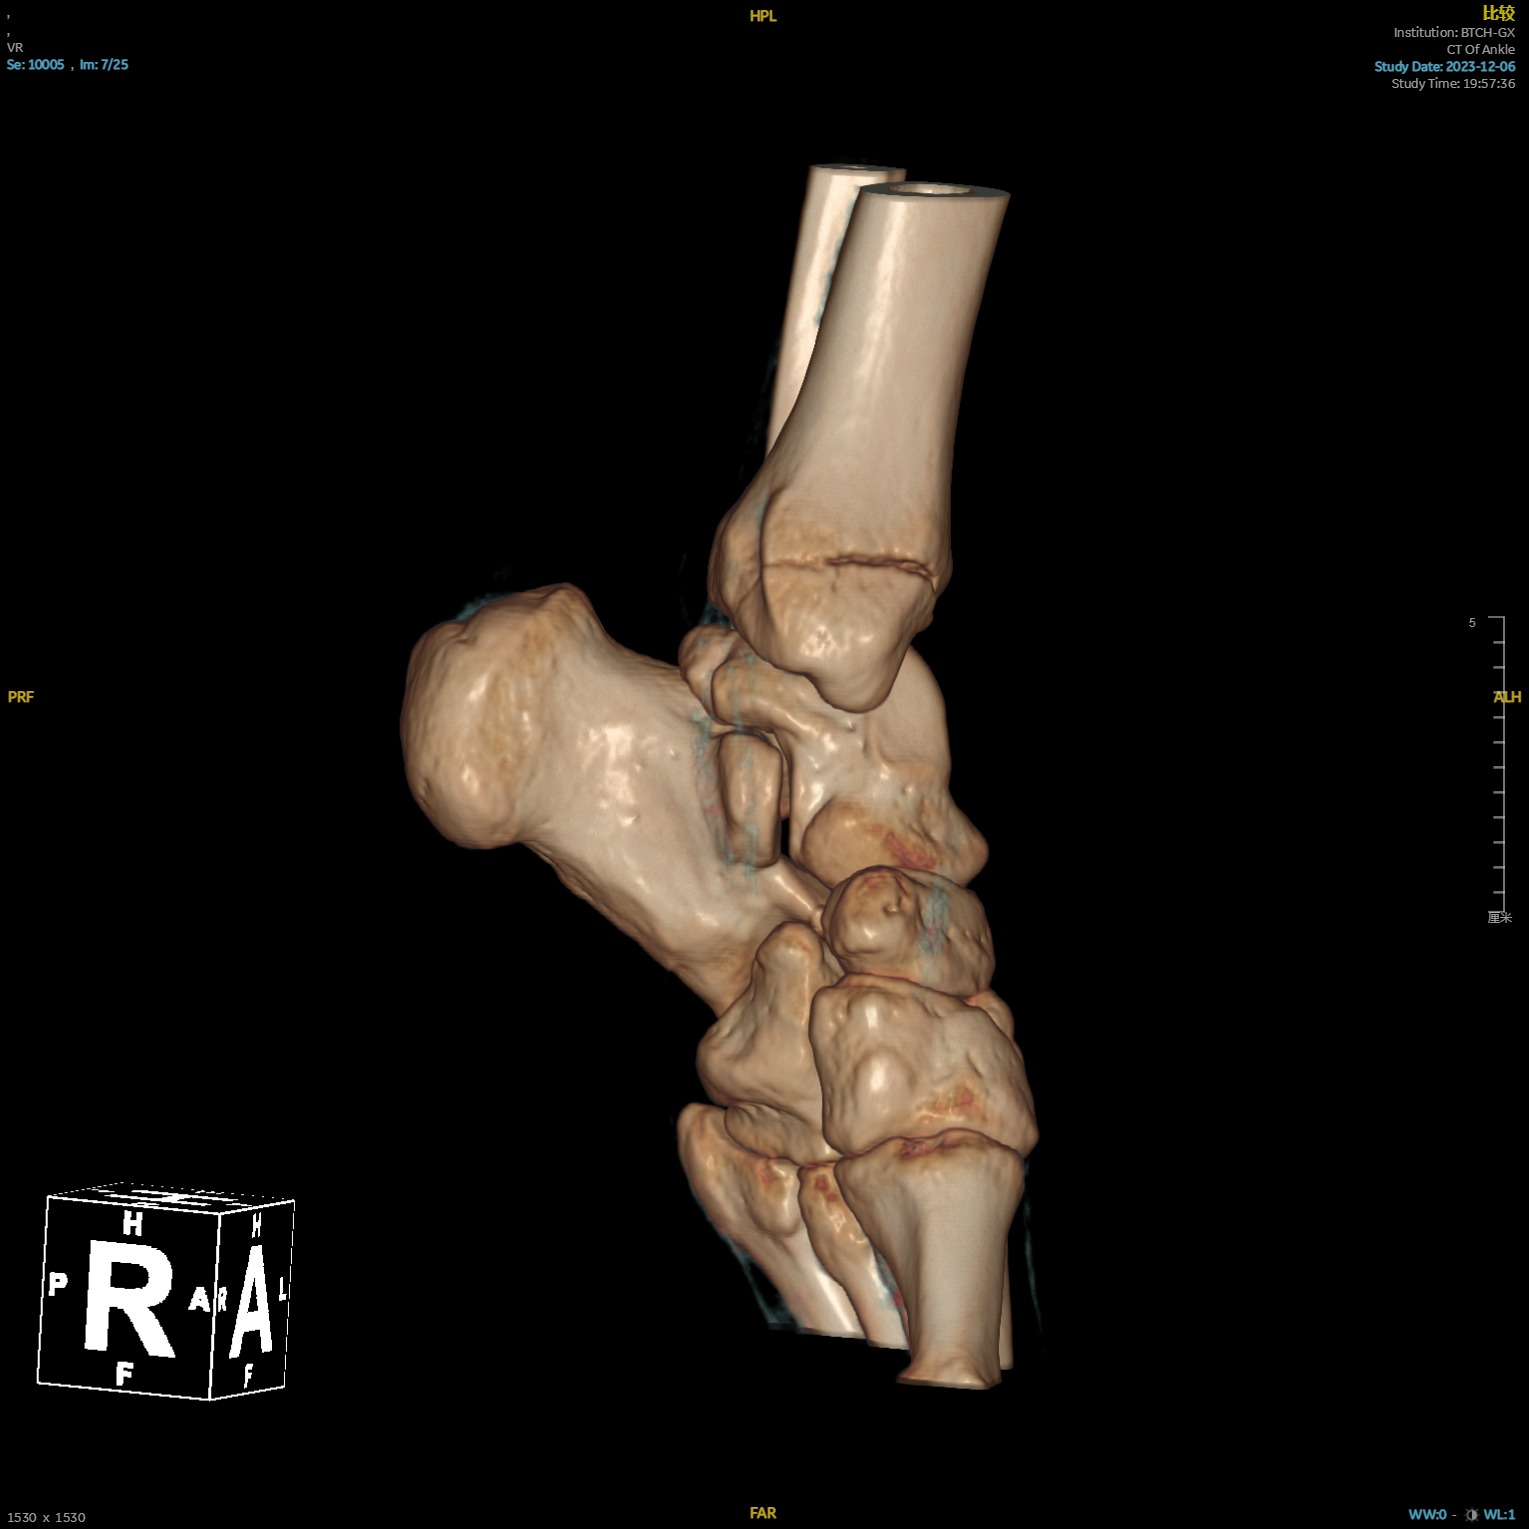

本次手术患者20岁,骑电动车时不幸发生车祸,导致其右侧髋部、左侧踝关节疼痛,随后来到北京清华长庚医院急诊就诊。经检查,患者被诊断为右侧髋臼骨折、右侧髂骨骨折、左侧踝关节骨折。

术前影像1.png  术前影像2.png  术前影像3.png

患者多处骨折影像资料